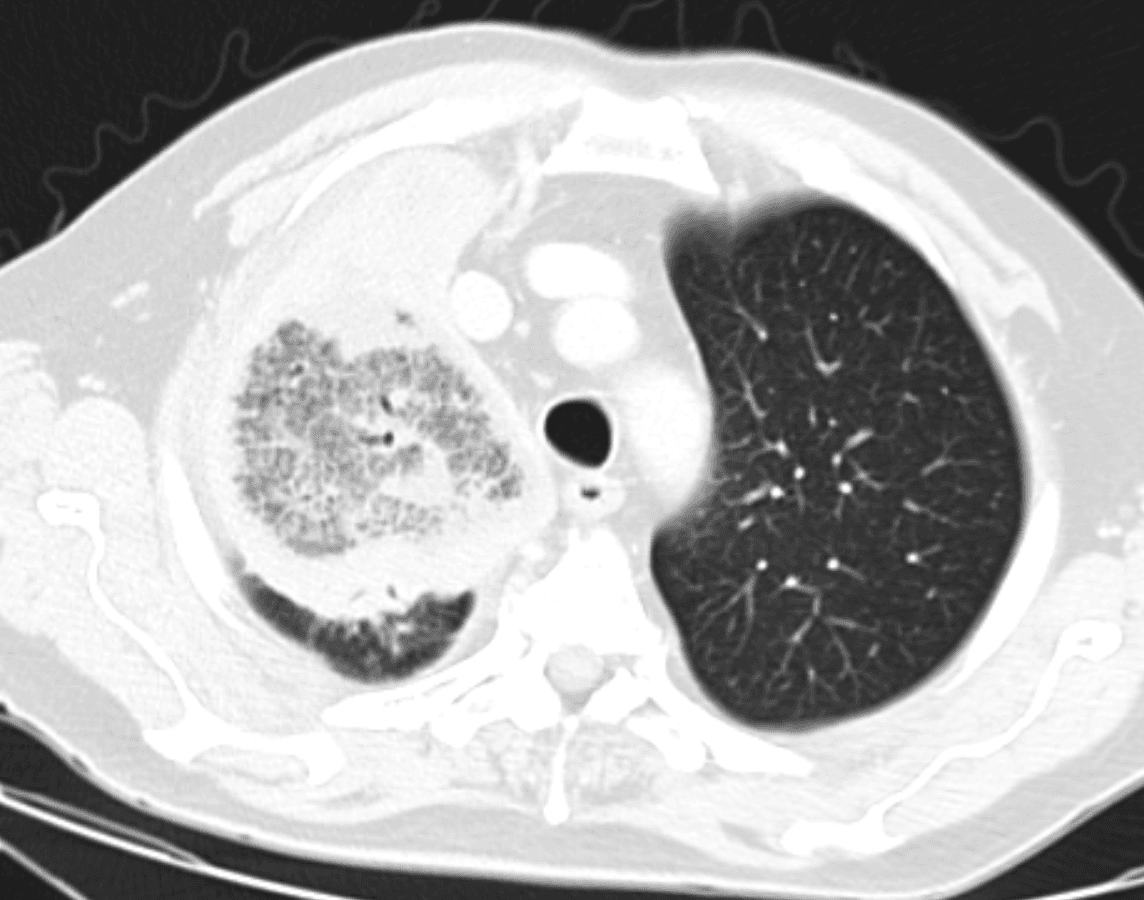

Laboratory studies show white blood cell count 17.4 x 10^3/uL, serum glucose 624 mg/dL, sodium 128 mmol/L, potassium 5.6 mmol/L, bicarbonate 9 mmol/L, anion gap 27, creatinine 1.8 mg/dL, lactate 2.4 mmol/L, beta-hydroxybutyrate 6.9 mmol/L, and venous pH 7.17, consistent with diabetic ketoacidosis. Hemoglobin A1c returns at 14.1%. Blood cultures remain negative, respiratory viral testing is negative, and serum galactomannan is not detected. Repeat chest radiography confirms a persistent right upper lobe opacity without pleural effusion. Chest CT demonstrates a focal right upper lobe consolidation with central ground-glass attenuation surrounded by a denser rim, creating a reverse halo sign.

Axial CT chest demonstrates a right upper lobe lesion with central ground-glass attenuation surrounded by denser peripheral consolidation, producing a reverse halo sign.